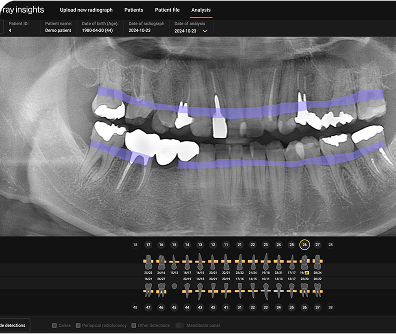

Align's X-ray Insights ist ein reines Software-Produkt zur computergestützten Erkennung (CADe), das KI einsetzt, um radiologische Auffälligkeiten automatisch zu analysieren und zu markieren. So können Sie Ihre wertvolle Zeit wieder dem widmen, was wirklich wichtig ist – Ihren Patienten eine hervorragende Versorgung anzubieten.

Align´s X-ray Insights nutzt fortschrittliche KI-gesteuerte Algorithmen und Deep-Learning-Techniken, um Ihr diagnostisches Potenzial zu erweitern - ohne Ihre Entscheidungsfreiheit einzuschränken.

KI-Befunde sind präzise und werden intuitiv in hoher Qualität als farbkodierte Anmerkungen direkt auf dem Röntgenbild und dem interaktiven Zahnschema angezeigt.

Entwickelt, um Sie durch eine fundierte Behandlungsplanung und die Früherkennung pathologischer Befunde von Röntgenaufnahmen zu unterstützen.1